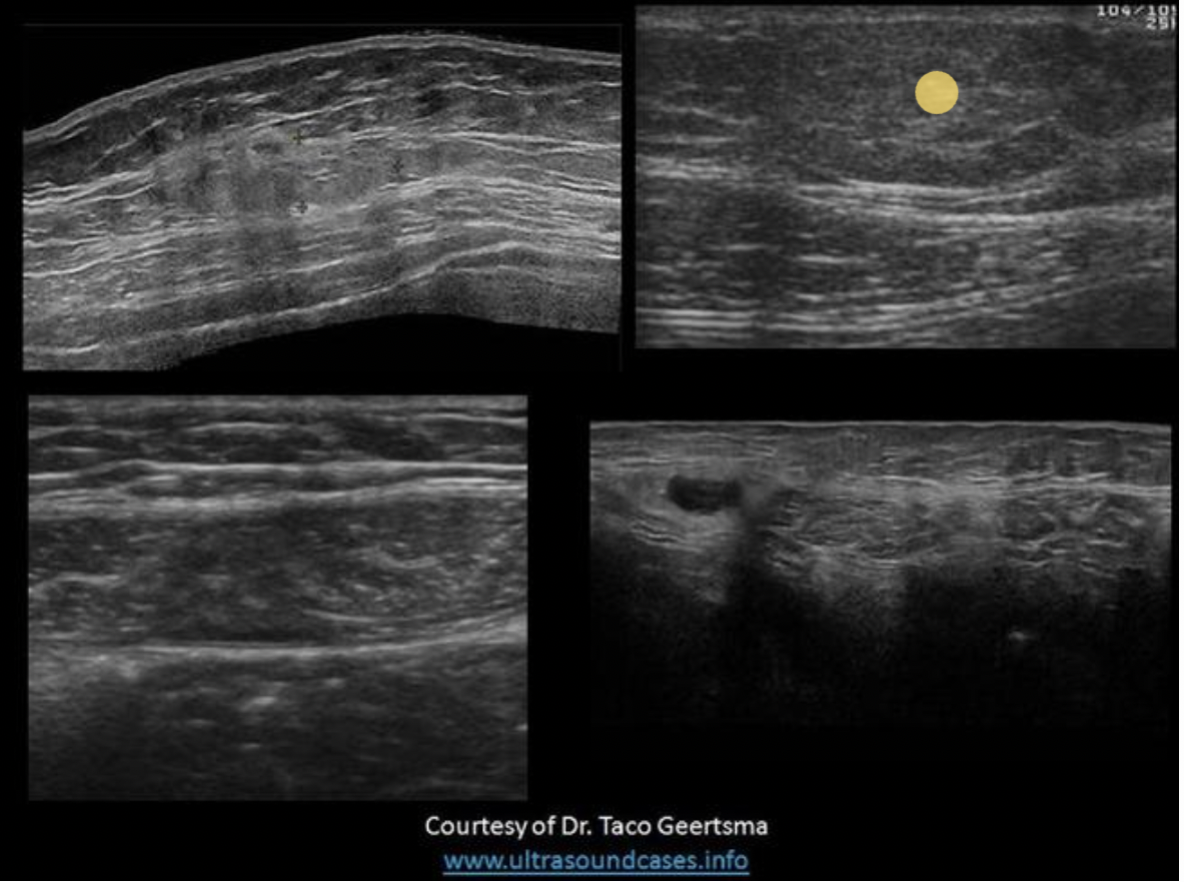

Find the rectus sheath hematoma

Top left is a benign mass with lobulated borders and the top right is a lipoma. Both are located in the subcutaneous tissues/fat between the skin and the anterior rectus sheath. The lipoma has smooth borders and an echogenicity similar to the surrounding fat.

The bottom right image demonstrates a spigelian hernia, between the right rectus abdominis and right oblique muscles.

The bottom left image demonstrates a hematoma in the rectus abdominis muscle, between the anterior and posterior rectus sheaths.

Find the lipoma

The top two images demonstrate solid masses that are superficial to the rectus abdominis muscle. Top left is a benign mass with lobulated borders and the top right is a lipoma. Both are located in the subcutaneous tissues/fat. The lipoma has smooth borders and an echogenicity similar to the surrounding fat.